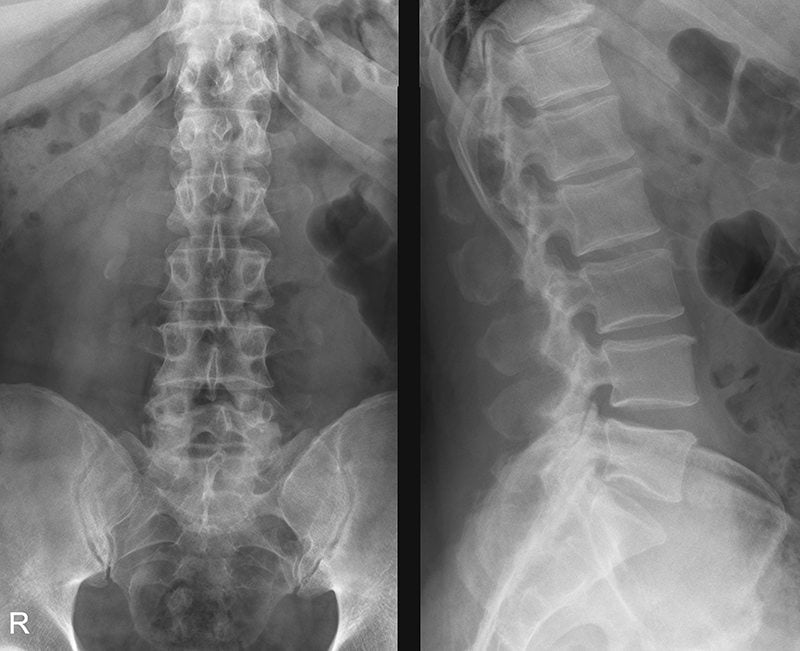

Рентгеновские снимки плат в высоком разрешении